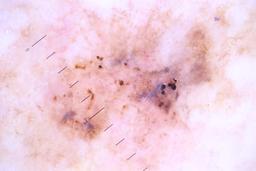

{

"age_approx": 85,

"anatom_site_general": "posterior torso",

"concomitant_biopsy": true,

"diagnosis_1": "Malignant",

"diagnosis_2": "Malignant melanocytic proliferations (Melanoma)",

"diagnosis_3": "Melanoma, NOS",

"diagnosis_confirm_type": "histopathology",

"image_type": "dermoscopic",

"lesion_id": "IL_1072654",

"melanocytic": true,

"patient_id": "IP_9746668",

"sex": "female"

}